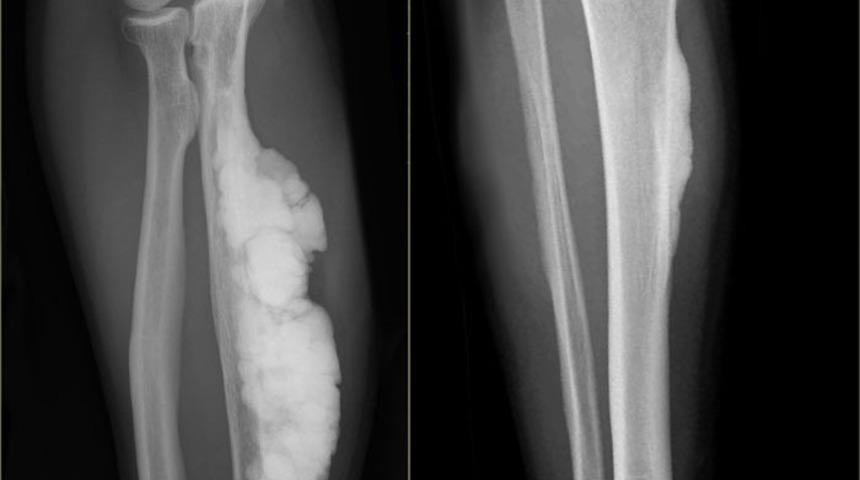

Röntgen Testleri İle Ortaya Çıkıyor

Kemiğin Paget Hastalığı’nın gözle görülür bir belirtisi yoktur. Hastalarda genellikle 40 yaşından sonra yapılan sağlık taramaları ve röntgen testleri ile birlikte ortaya çıkabilir ve en sık rastlanan belirtisi kemik ağrısıdır. Yapı olarak bozuk iskelet dokusu gelişir ve bu da kırık riskinde artışla birlikte kemikte şekil bozukluğuna neden olur.